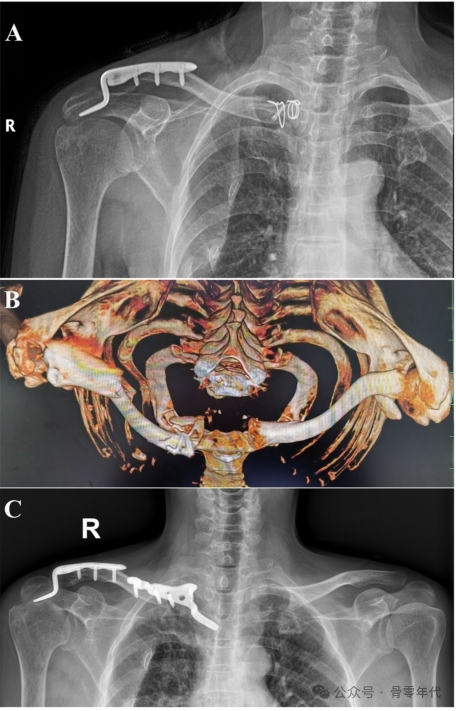

一名56岁的保安在从电动自行车上摔下,右肩疼痛来到医院就诊。在患者的标准X线片上,锁骨骨折的近端和远端均被分离。CT从不同角度显示锁骨骨折移位情况。术后骨折线、脱位均恢复。

1例锁骨远端骨折伴锁骨近端脱位患者的影像表现。钢板内固定治疗双极锁骨损伤1例。利用杠杆复位锁骨两端,然后分别放置新的胸锁钢板和肩锁钢板。术后对患者进行影像检查。X线和CT图像